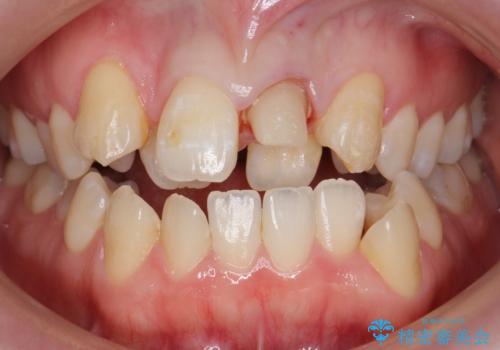

前歯が黒い セラミックで綺麗に 20代女性

- 前歯が黒くなってきたことを主訴に来院された患者様です。

精査したところ、う蝕により歯の内側から黒くなっていました。

※重度叢生のため矯正治療や機能していない歯の抜去を提案致しましたが、ご希望されませんでした。